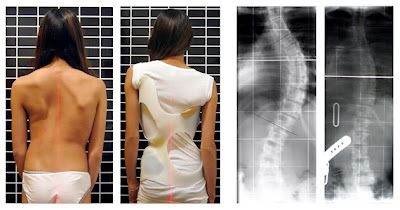

so, haini mak nak story mory ngan uols pasal sakit belakang.. mak konpiden sangat uols sume penah rasa sakit belakang kannn.. alaaa.. kalao uols rasa sakit or kurang selesa, especially kat bahagian bawah badan- sakit belakang laa tu..

actually ade beberapa sebab terjadinya sakit tulang belakang ni.. antaranya:

macam gini la keadaan tulang belakang yang boleh menyebabkan kesakitan akibat daripada stress..